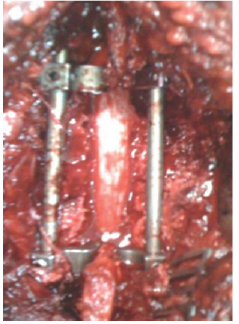

The embolization of the aneurysm has been excluded from the management plane, because the spinal cord needed urgent surgical decompression. The patient sent to the OR for urgent spinal cord decompression surgery, complete T10 laminectomy with excision of the mass in the right lamina pedicle and T9-T10 facet joint was performed. Segmental T9-T10 fixation and fusion was done as showen in (Figure 8 & 9)

Figure 8:

Figure 9: